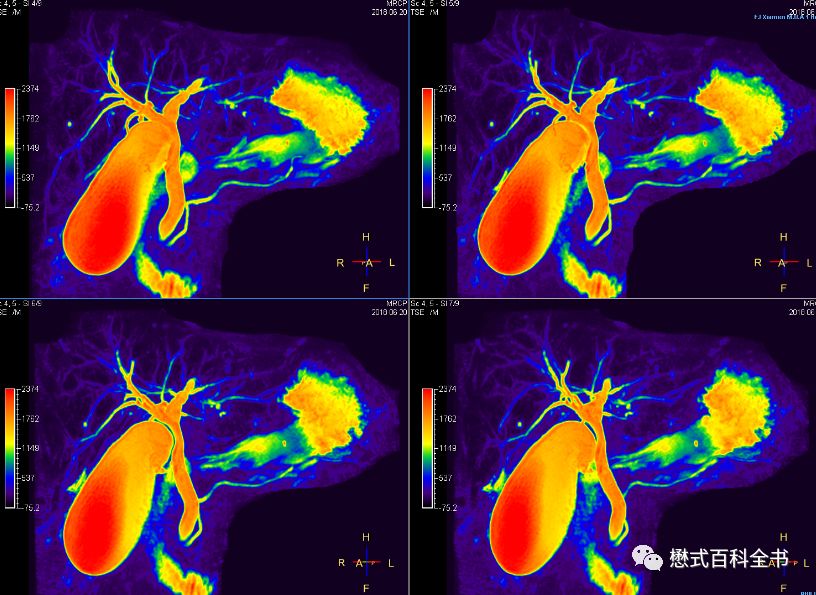

图22:2D MRCP扫描

如图,2D单激发MRCP扫描。一次激发采集一层或者多层。

2D MRCP优点是:扫描速度快。一次激发采集1层或者多层,直接出图像,能够很好的显示结石的充盈缺损。

缺点是:信噪比比3D的低,一次扫描出1~几层,单层层厚厚,有部分容积效应。

所以,理论上为了保证好的诊断效果,我们推荐3D MRCP和2D ssh MRCP都要扫描。当然,3D MRCP扫描完,一定要看原始薄层图像,有经验的诊断医生不可能只看MIP图去诊断。